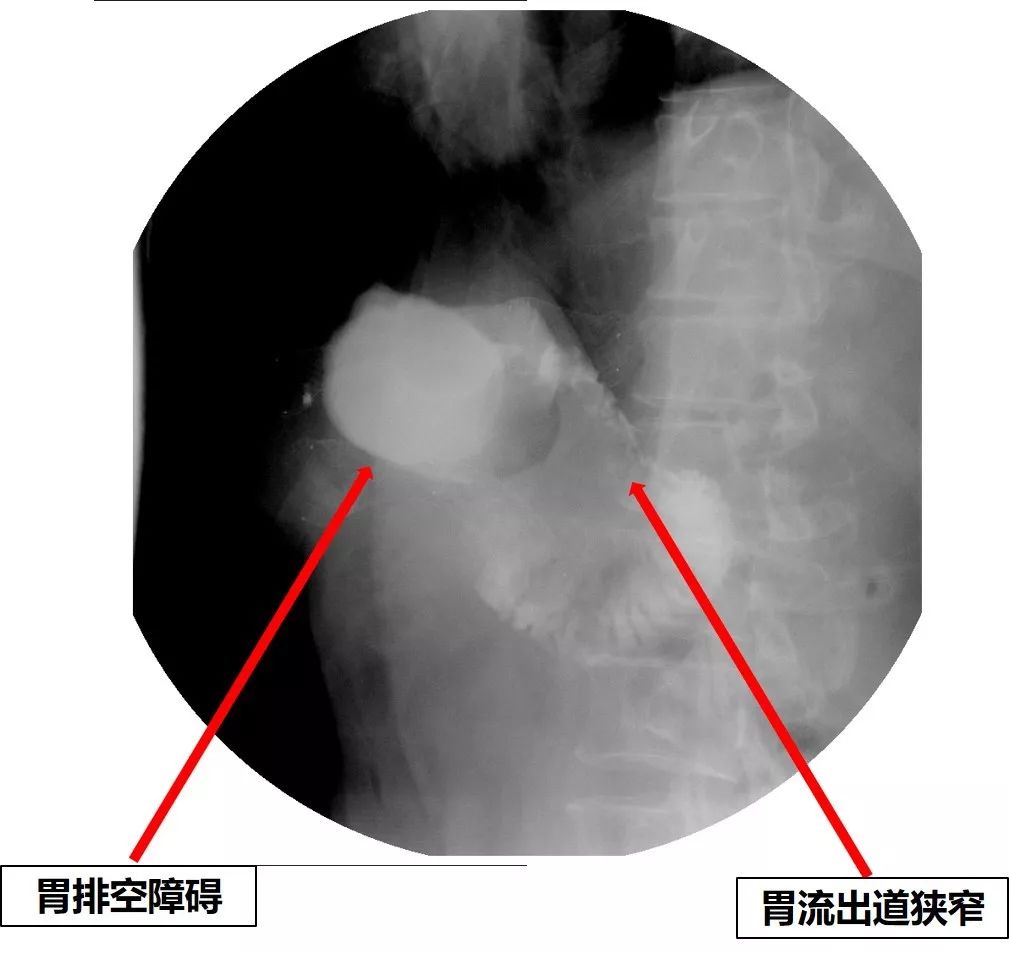

2018年9月底,患者恶心、呕吐症状再次加重,呕吐物为胃内容物,不能进食水,伴反酸、烧心,为进一步治疗来诊。X线腹部平片未见肠梗阻。上消化道造影检查见胃排空障碍,结合之前的内镜检查结果,考虑胃流出道梗阻(图16)。

图16 上消化道造影见胃排空障碍,流出道狭窄

但是,患者出于美观和舒适度的考虑,坚决要求放置肠道支架(胃流出道支架)。于是,在2018-9-30为患者放置了胃流出道支架。术中见胃内有大量胃液潴留,吻合口前区狭窄,前壁肿物隆起,内镜通过困难。证明术前判断是正确的。术后第二天,上消化道碘油造影见胃排空较前加快,支架位置良好,造影剂通过支架顺畅(图17)。